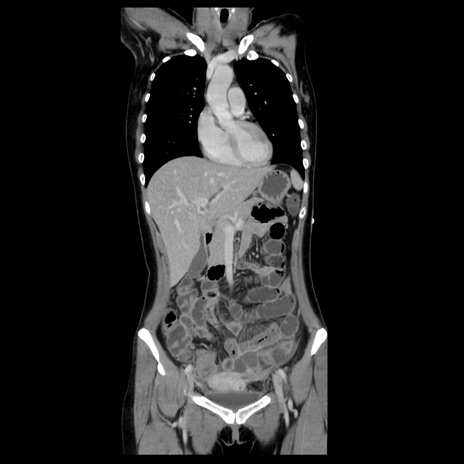

症例39(冠状断像)

【症例】40歳代女性

【主訴】上下腹部痛

【現病歴】2日目から下腹部痛あり。夜間は痛みで眠れなかった。昨日より上腹部痛と下痢が出現。臥位で痛みは軽快したため、休んでいた。本日になって臥位でも立位でも痛みが強くなってきたため救急要請。

【既往歴】子宮内膜症

【身体所見】部:平坦・軟、左上下腹部に圧痛あり、反跳痛あり。

【データ】WBC 21800、CRP 26.78

CT